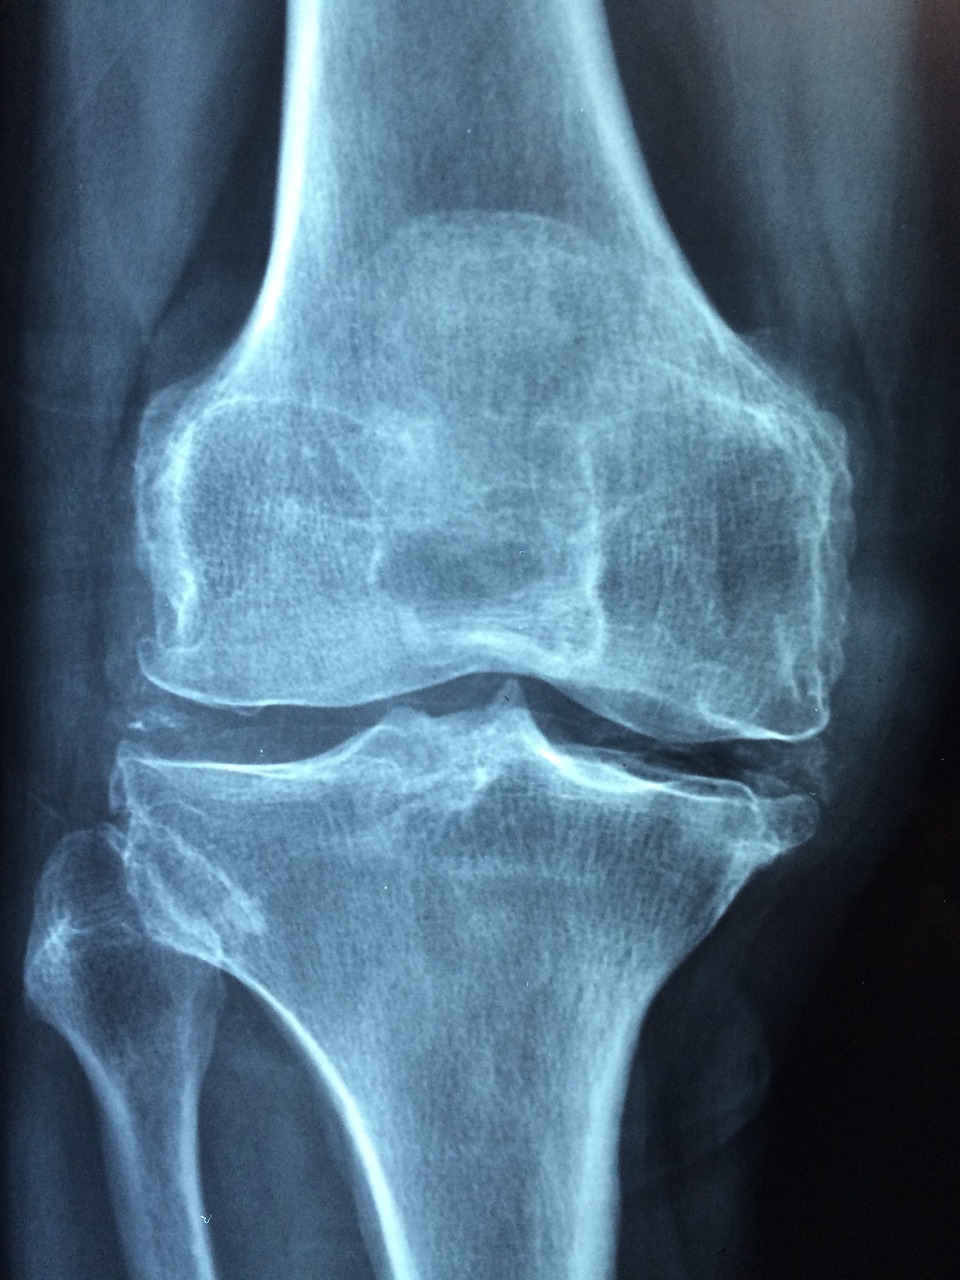

주로 무릎, 어깨, 손목 등 관절 기능 저하 또는 퇴행성 관절염 등이 있을 때 도움이 되며, 일반적으로 글루코사민, 콘드로이틴, MSM, 콜라겐, 오메가-3와 같은 성분이 함유되어 있습니다.